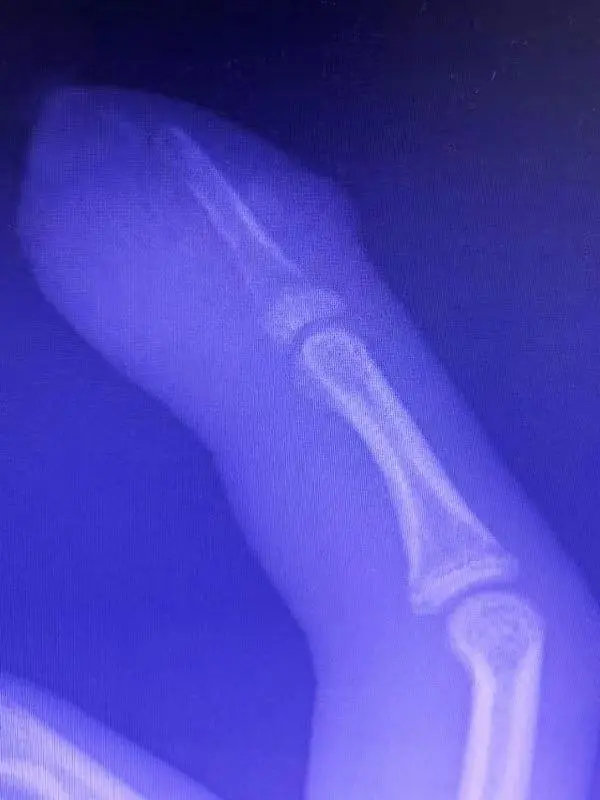

經過醫生初步檢查後,診斷少年患上了急性骨髓炎,推測應該是口腔裡的細菌順著傷口從而侵入手指內部導致感染。此外,醫生指出,少年不止細菌感染,還出現了皮膚化膿,X光片也顯示出部分指骨組織因感染出現壞死的跡象,情況一度嚴重之際,只能快速安排手術治療。

在手術過程中,醫生幫少年排除膿液,清理壞死骨組織,所幸手術成功,少年順利保住手指,醫生表示如果再置之不顧幾日,恐怕難逃截肢命運。